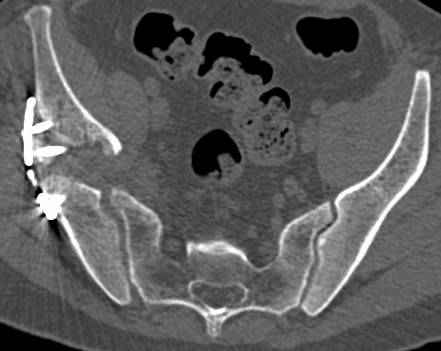

высылаю дополнительно сканы.

Судя по представленным реконструкциям (не очень хорошего качества - много наводок)

мы имеем дело с полупоперечным переломом у которого отломался задний край или его отломали, превратив перелом в полный двухколонный.

По отдельным срезам и тем более по реконструкции трудно судить о сращении крыла и задней колонны с осевым скелетом.

Все выступающие коллеги высказались насчет необходимости стандартных снимков по Judet, потому что для определения тактики лечения переломов вертлужной впадины 3Д снимки малоинформативны.

Из того минимума, что представлено, мне кажется, мы имеем дело с двухколонным переломом вертлужной впадины. Обычно медиальный (центральный) "вывих" головки встречаются в сложных двухколонных переломах со смещением.

Дополнительные сканы